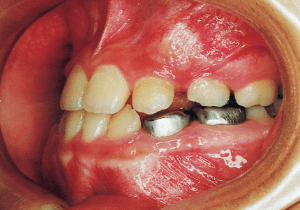

The Edgewise appliance was applied locally (8) and removed after 11 months (9). However, as the maxillary molar region gradually became crossbite, the maxillary arch was laterally expanded using a quad helix.

A case of diverted and cross bite during the deciduous dentition. Despite early treatment, the deviation progressively worsened with age, necessitating surgical treatment. At the initial visit, the patient had a deciduous dentition, and observation was planned (3). With the eruption of the permanent incisors, the mandible shifted slightly to the right, resulting in a cross bite (1) At this point, asymmetry can be confirmed in the front view. However, it is slight. The cephalometric X-ray reveals a structure with a slightly dominant mandible, but asymmetry in the mandibular ramus is not observed.